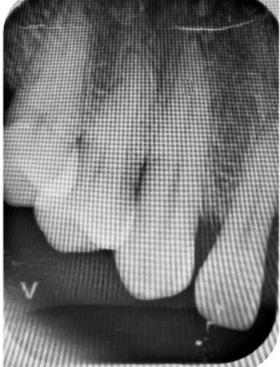

Figura 2. Radiografías periapicales de órganos dentarios con posibilidad de mantenerse en boca.

hace 8 años por lo que toma 30 mg de nifedipino cada 12 horas, amlodipino 5 mg cada 24 horas, telmisartan 40 mg cada 12 horas y metropolol 100 mg cada 12 horas, además comenta padecer diabetes mellitus tipo II desde hace 7 años por lo que también toma 50 mg de metformina cada 12 horas y dapagliflozina 10 mg cada 24 horas. Clínicamente se observó una encía roja y sangrante, profundos sondeos, una notable hiperplasia gingival, depósitos de cálculo y movilidad dental grado III en todos los órganos dentarios a excepción del segundo premolar superior derecho al canino superior izquierdo, quienes presentaban una movilidad grado II. Radiográficamente se encontró una pérdida de inserción radiográfica avanzada generalizada

en la arcada inferior, y grupos molares de ambos cuadrantes superiores (Figura 1), los únicos órganos dentarios con posibilidad de preservación en boca a través de terapia periodontal se encontraron en el sector anterior de la arcada superior anteriormente mencionados con movilidad grado II